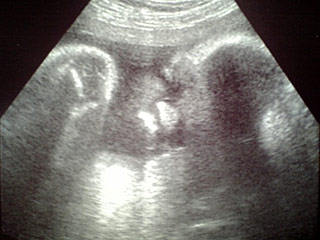

なお写真は、2日前に撮影した骨付きチキンちゃんです。

首を左にかしげてます。

よく産まれたての赤ん坊は元某ボクサーそっくりといいますが、そっちよりもむしろ「オルメカの巨石像」のほうが似ている気がする……

赤ちゃんって実は天然M字開脚

この角度、なんとなくはずかしっ、と思うかーちゃんは、なんか間違ってますか